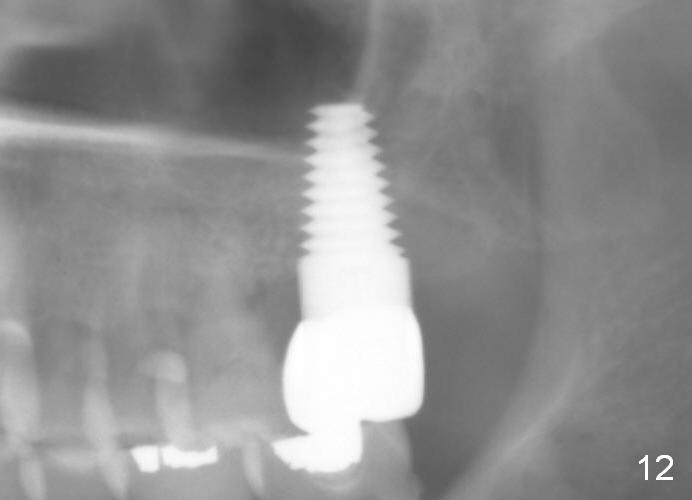

Model study shows that the implant is placed distally (Fig.9,11) in addition to buccal implant exposure (Fig.10 arrowheads). Postop, the patient complains of upper left discomfort, which is more likely associated with furcal infection of the tooth #14. The symptom disappears after use of water pik. Panoramic X-ray is taken 6 months post cementation (Fig.12).